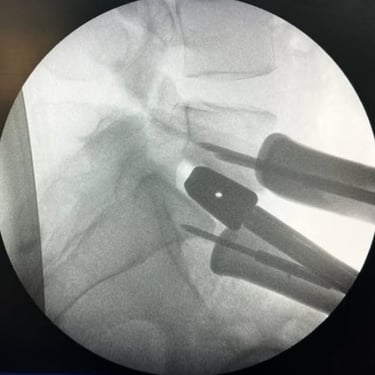

La cirugía ALIF (Anterior Lumbar Interbody Fusion), o Fusión Lumbar Intercorporal Anterior, es una técnica quirúrgica utilizada para tratar patologías de la columna lumbar como la degeneración discal, la inestabilidad vertebral o las hernias lumbares recurrentes. Mediante un abordaje anterior, se extrae el disco dañado y se coloca un injerto o caja intersomática que permite lograr la fusión estable entre las vértebras. Este procedimiento favorece una mejor restauración del espacio discal, alineación lumbar y preservación muscular. La cirugía ALIF es realizada por un equipo especializado en neurocirugía de columna, garantizando precisión y resultados funcionales óptimos.